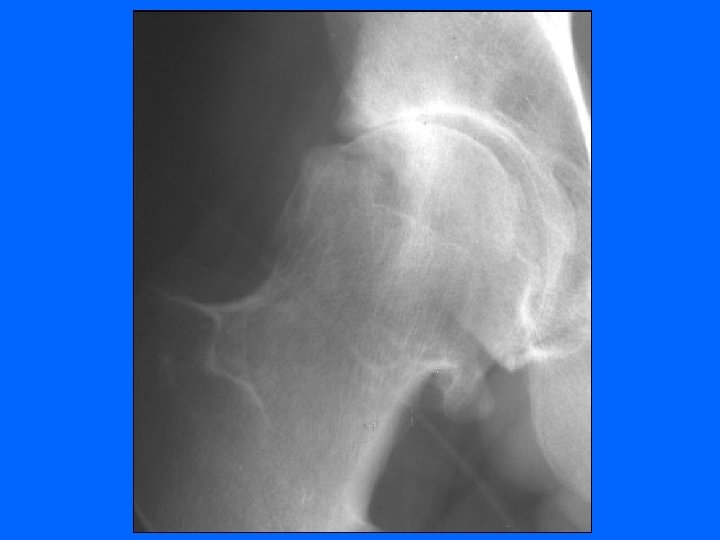

Coxarthrose Clinique • Debout – Recherche boiterie, – Attitude vicieuse, en flexum ou en rotation externe • Couché – douleur et/ou limitation douloureuse lors mobilisation (flexion / RI / RE) • La radiographie – Cliché bassin debout de face – Profil